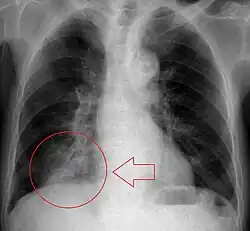

Chest X-rays can be useful in the diagnosis of aspiration pneumonia but may be negative early in the course.[12] Chest CT Scan can identify the presence of a pneumonia as well, and can also assist in characterizing abscesses, foreign objects, or pleural disease.

Aspiration seen on barium swallow study.

A fluoroscopic swallow study can be done in cases where dysphagia or motility disorders are thought to be the source of aspiration. Food and drink are mixed with barium contrast and monitored using x-ray to evaluate swallowing. Aspiration can be diagnosed if contrast is seen coursing below the vocal cords into the trachea.[13]